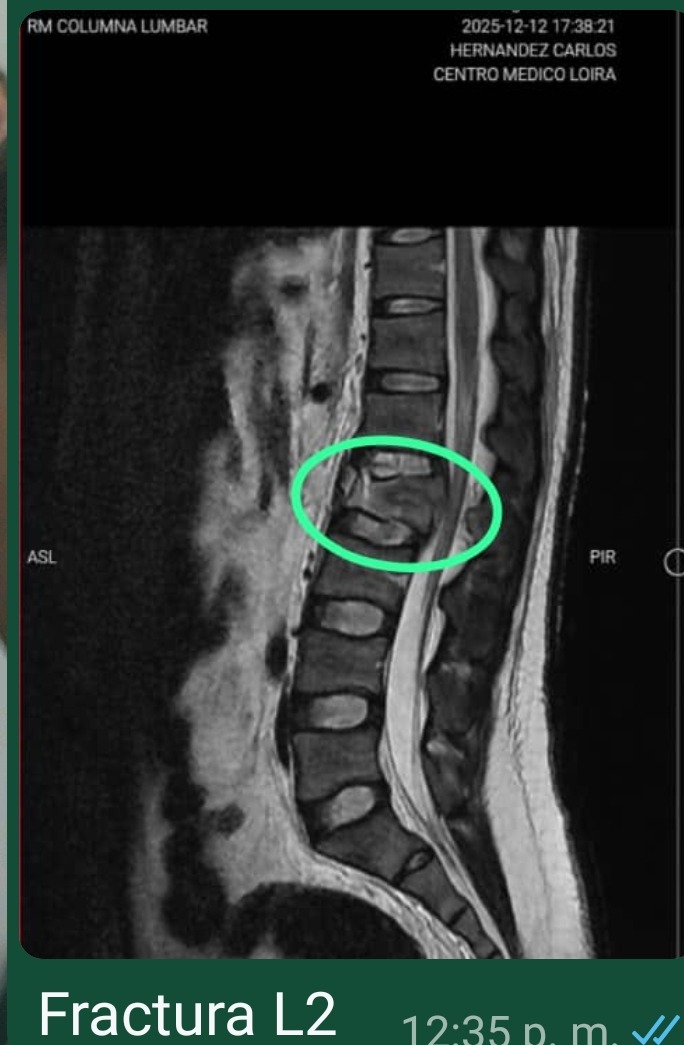

Hola soy Díany la Mamá de Carlos Hernández, de 35 años, mi hijo sufrió un grave accidente en motocicleta el día 6 de Diciembre el cual le dejó como consecuencia tres fracturas : Pelvis, Columna (L2), brazo Izquierdo (Cubito y Radio) y Quemaduras de 1er. Grado en el 60 % de su espalda. De las cuales ya afortunadamente le han practicado dos de las tres operaciones Pelvis y Brazo Izquierdo, quedando pendiente y con carácter de urgencia La Operación de Columna Vertebral (L2), valorada en 5000 $, motivo por el que me dirijo a cada persona que pueda aportar su granito de arena para esta causa porque ya no contamos con recursos económicos.